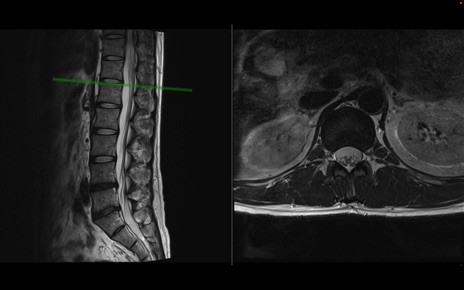

【整形】TIPS症例1 腰椎MRI 横断像と矢状断像

【症例】40歳代男性

【主訴】左臀部〜大腿後面痛み

【現病歴】2週間前から腰痛あり。2日前に夜中にくしゃみをした際に激痛が出現。疼痛強いため来院。

【身体所見】左臀部〜大腿後面、下腿後面のしびれ。SLR -/+ 30度、うつ伏せ困難、筋力低下なし。

異常所見と診断は?